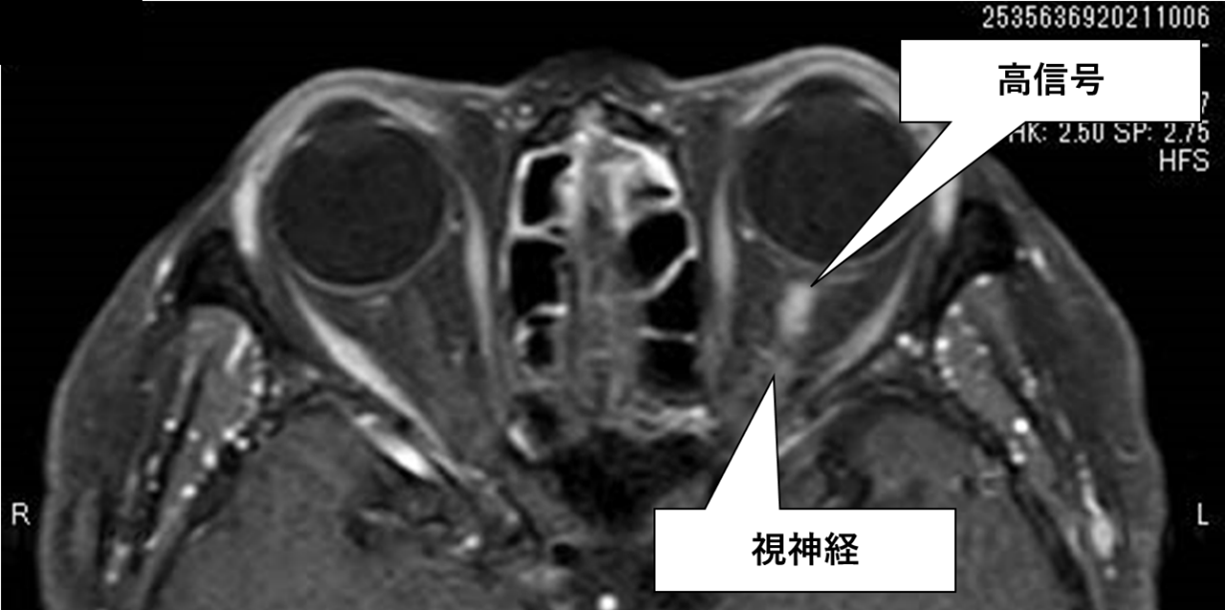

初めて視神経炎の症状を示した人は、視神経と脳の画像検査を受ける可能性があります。

CT またはMRIスキャンは、医師がその人が MS であるかどうかを判断するのに役立ちます。脳内の病変の存在はこの状態の兆候です。